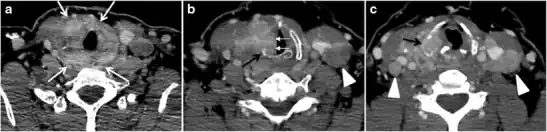

The radiologist must evaluate the central structures draping the thyroid gland including the trachea, oesophagus, larynx, and pharynx, as well as the recurrent laryngeal nerve. Invasion is suspected if the thyroid mass abuts the airway or oesophagus for more than 180 degrees. Luminal deformity, mucosal thickening and mucosal focal irregularity are more specific indicators of invasion. Obliteration of the fat planes of the tracheoesophageal groove in three axial images and signs of vocal cord paralysis are indicative of recurrent laryngeal nerve invasion. Invasion of these central structures meets the criteria for T4a disease (Figs. 5 and and6)6).[1]

Arterial invasion constitutes T4b disease, which may preclude curative surgery. More than 180 degrees of arterial encasement is suggestive of invasion, however, arterial deformity or narrowing is much more suspicious for invasion. The carotid artery is the most commonly involved artery; however, the mediastinal vessels should also be examined. Encasement of the carotid artery or mediastinal vessels for more than 270 degrees is unlikely to be resectable. On the other hand, occlusion or effacement of the internal jugular vein can occur without invasion and does not influence surgical resectability or staging. Asymmetry of the strap muscle and the tumour abutting its external surface are signs of an invasion. However, invasion of the pre-vertebral musculature is more challenging, as a large lesion can compress the muscle without invasion (Figs. 5 and and6)6).[1]

Finally, the possibility of metastatic disease should be excluded. PTCs and medullary thyroid carcinomas tend to metastasize to regional lymph nodes. According to the AJCC/UICC TNM staging system, the nodal stage is classified by site: N1a indicates level VI nodal involvement, including paratracheal nodes; N1b indicates unilateral or bilateral lateral cervical nodal disease or superior mediastinal nodal disease (Figs. 4, 55 and and6)6).[1]